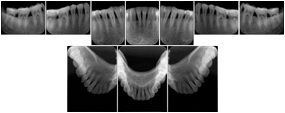

OO.1.4 Radiology

• A radiologist on his PACS assembles a screen layout of a stack of CT images of a current lung study, a secondary capture of a 3-D rendering of the CT, and a prior chest radiograph for the patient. He adjusts the window width / window level for the CT images, and zooms and annotates the radiograph to clearly indicate the tumor. He saves a Structured Display object representing that screen layout, including Grayscale Softcopy Presentation State objects for the CT WW/WL and the radiograph zoom and annotation. During the weekly radiology department conference, on an independent (non-PACS) workstation, he accesses the Structured Display object, and the display workstation automatically loads and places the images on the display, and presents them with the recorded WW/WL, zoom settings, and annotations.

• A mammographer reviews a screening exam on a mammo workstation. She wishes to discuss the exam with the patient's general practitioner, who does not have a mammo-specific workstation. She saves a structured display, with presentation states for each image that replicate the display rendered by the mammo workstation (scaling, horizontal and vertical alignment, view and laterality annotation, etc.).

Mammography Structured Display

Figure OO-7. Mammography Structured Display